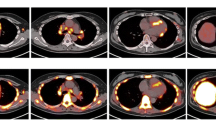

Representative transversal dynamic images of 18F-FAMT and 18F-FDG are shown in Figure 1. The uptake of 18F-FAMT gradually decreased in both granulomas and tumours (Figure 1a). In contrast, the uptake of 18F-FDG gradually increased in both lesions (Figure 1b). The time-activity curves of the mean SUVs of 18F-FAMT and 18F-FDG in each VOI are shown Figure 2. In the tumours, 18F-FAMT showed a shoulder peak immediately after the initial distribution (6 to 15 min and 2 min p.i., respectively), followed by gradual clearance, whereas in the granulomas, 18F-FAMT showed slow, exponential clearance after the initial distribution (2 min; SUV: 1.69 ± 0.25). The dynamic pattern of 18F-FAMT uptake in the tumours was significantly different from that in the granulomas or muscles (Figure 2a, p < 0.001). The dynamic pattern of 18F-FAMT uptake between granulomas and muscles showed no significant differences. The time-activity curves of 18F-FDG in the granulomas and tumours exhibited similar patterns and showed no significant differences (Figure 2b).

Static images of 18F-FAMT-PET and 18F-FDG-PET at 60 min after administration are shown in Figure 3a,b. Visual and SUV assessments of the static images were unable to differentiate tumours from granulomas in all cases, owing to overlaps in 18F-FAMT uptake, although the mean SUV in the granulomas (0.88 ± 0.12) was significantly lower than that in the tumours (1.00 ± 0.10, p < 0.001, Figure 3c). The static images and the mean SUVs of 18F-FDG in the granulomas were similar to those in the tumours (tumour vs. granuloma: 4.25 ± 0.93 vs. 4.00 ± 0.59, p = 0.37, respectively, Figure 3d).

Static 18F-FAMT (a) and 18F-FDG (b) images in rats bearing granuloma and tumour. Transverse, coronal and sagittal images of 18F-FAMT and 18F-FDG (50 to 60 min). White arrow: locations of C6 tumour (right) and granuloma (left). Individual values of SUV for 18F-FAMT (c) and 18F-FDG (d) in granuloma and tumour lesion (50 to 60 min p.i.). Significant differences were determined (**p < 0.005; N.S., not statistically significant).